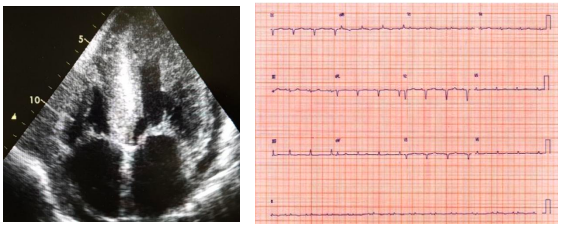

Mulher de 53 anos com quadro de dispneia aos mínimos esforços, hepatomegalia, ascite e edema de membros inferiores há 5 meses. Nega história familiar de cardiopatia. Realizou o ecocardiograma e o eletrocardiograma a seguir:

Considerando essas informações, a hipótese diagnóstica mais provável é